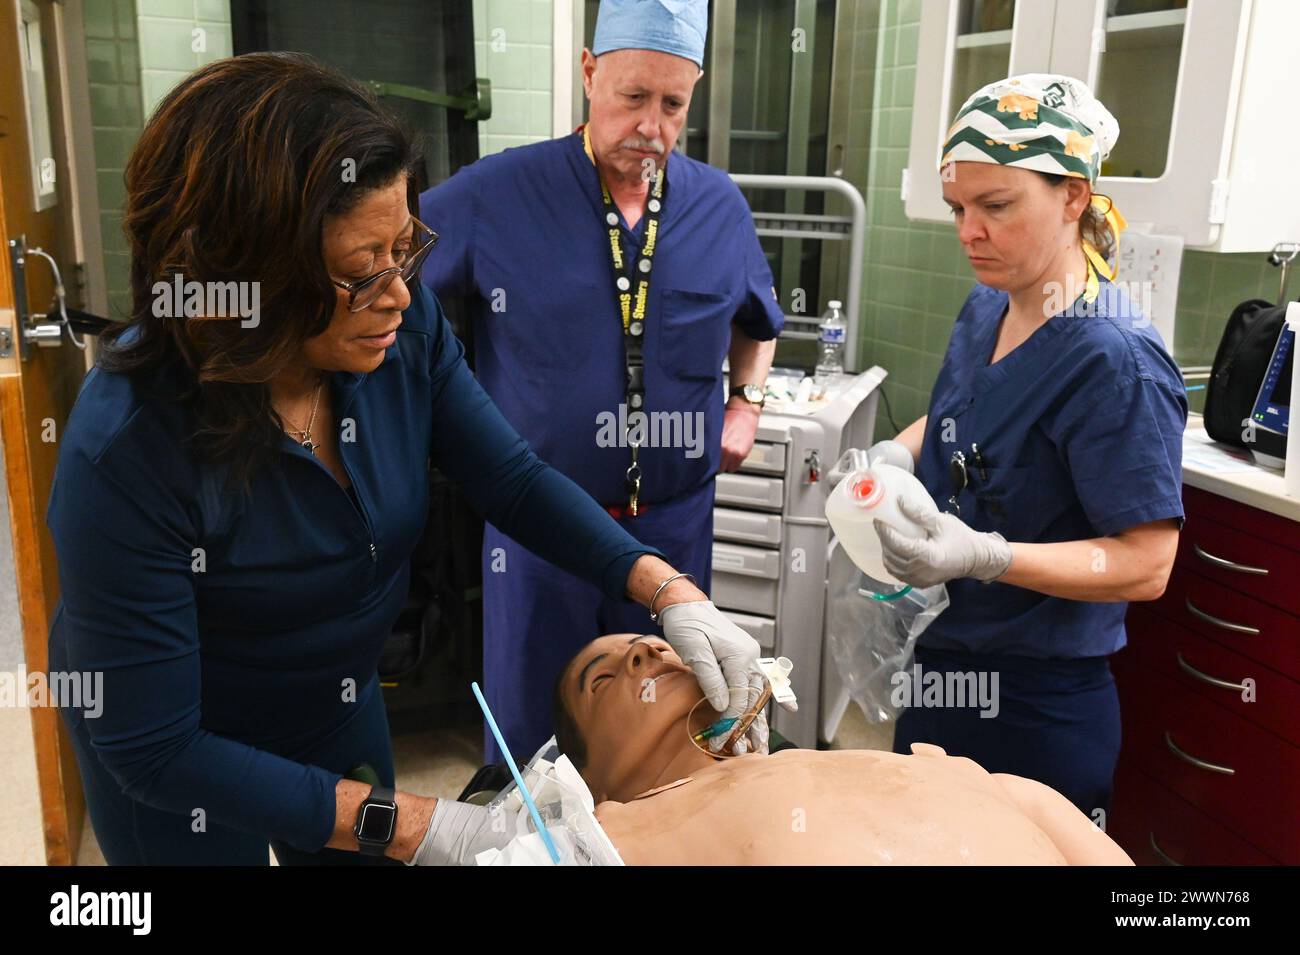

The Kimbrough Ambulatory Care Center Anesthesia Care Team simulated various methods of performing an emergency cricothyrotomy, Fort Meade, Maryland, Feb. 5, to validate providers' skills and update credentials. A cricothyrotomy is an incision made through the skin and cricothyroid membrane to establish a patent airway during certain life-threatening situations, such as airway obstruction by a foreign body, angioedema, or massive facial trauma. Defense Health Agency Stock Photohttps://www.alamy.com/image-license-details/?v=1https://www.alamy.com/the-kimbrough-ambulatory-care-center-anesthesia-care-team-simulated-various-methods-of-performing-an-emergency-cricothyrotomy-fort-meade-maryland-feb-5-to-validate-providers-skills-and-update-credentials-a-cricothyrotomy-is-an-incision-made-through-the-skin-and-cricothyroid-membrane-to-establish-a-patent-airway-during-certain-life-threatening-situations-such-as-airway-obstruction-by-a-foreign-body-angioedema-or-massive-facial-trauma-defense-health-agency-image600985198.html

The Kimbrough Ambulatory Care Center Anesthesia Care Team simulated various methods of performing an emergency cricothyrotomy, Fort Meade, Maryland, Feb. 5, to validate providers' skills and update credentials. A cricothyrotomy is an incision made through the skin and cricothyroid membrane to establish a patent airway during certain life-threatening situations, such as airway obstruction by a foreign body, angioedema, or massive facial trauma. Defense Health Agency Stock Photohttps://www.alamy.com/image-license-details/?v=1https://www.alamy.com/the-kimbrough-ambulatory-care-center-anesthesia-care-team-simulated-various-methods-of-performing-an-emergency-cricothyrotomy-fort-meade-maryland-feb-5-to-validate-providers-skills-and-update-credentials-a-cricothyrotomy-is-an-incision-made-through-the-skin-and-cricothyroid-membrane-to-establish-a-patent-airway-during-certain-life-threatening-situations-such-as-airway-obstruction-by-a-foreign-body-angioedema-or-massive-facial-trauma-defense-health-agency-image600985198.htmlRM2WWN6N2–The Kimbrough Ambulatory Care Center Anesthesia Care Team simulated various methods of performing an emergency cricothyrotomy, Fort Meade, Maryland, Feb. 5, to validate providers' skills and update credentials. A cricothyrotomy is an incision made through the skin and cricothyroid membrane to establish a patent airway during certain life-threatening situations, such as airway obstruction by a foreign body, angioedema, or massive facial trauma. Defense Health Agency